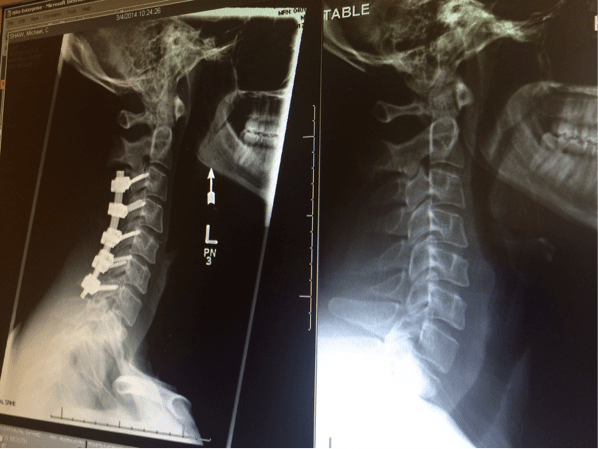

To date, his comeback story from a serious spinal cord injury has inspired many. Despite a doctor’s prognosis that he would never walk again, he took his first steps within three months and within the year, he was able to return to the mountains and ski. With his new book “Never Part of the Plan”, he weaves between telling his own story and how we can all learn from that personal experience. Below, Mike unpacks five of his keys to shift fear into growth.

On December 16th, 2013, life as Mike Shaw knew it changed in an instant. Skiing in Keystone, Colorado, he had a severe accident in which he dislocated and broke his neck. Paralyzed from the neck down, he was told he might never walk again. Following him throughout his inspiring story of recovery and triumph, The Healing Agent documents his success in adjusting to a new way of life and finding his way back to the mountains. You can check out the film in the above player.